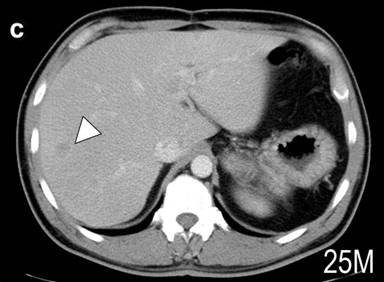

Figure 1. CT scan image of the abdomen. a. Large tumor was found at the tail of the pancreas (arrow heads). The CT scan of the liver 19 months (b.) and 25 months (c.) after the operation. Arrowheads indicate one of the metastatic tumors. The size appeared unchanged at 25 months. |

After the operation, VIP and calcitonin levels were decreased to 44 and 553 pg/mL, respectively, and diarrhea disappeared. Twelve months after the operation, however, the calcitonin level was gradually increased, and 19 months it reached at 3,980 pg/mL. CT demonstrated several small metastatic tumors in the liver (Figure 1b). Treatment with intramuscular injection of long-acting octreotide at a dose of 20 mg/month was started. Twenty-five months, the calcitonin was reduced to 803 pg/mL, and the patient has no endocrine symptom. The sizes of metastatic tumors in the liver appear unchanged (Figure 1c).